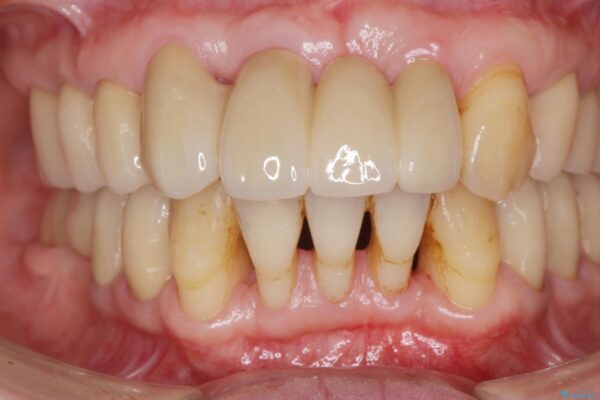

治療後

歯の総合的なマネージメントを行う包括的歯科治療の実践[ 歯周病・矯正・セラミック補綴 ] 治療後画像 歯の総合的なマネージメントを行う包括的歯科治療の実践[ 歯周病・矯正・セラミック補綴 ] 治療後画像 歯の総合的なマネージメントを行う包括的歯科治療の実践[ 歯周病・矯正・セラミック補綴 ] 治療後画像 歯の総合的なマネージメントを行う包括的歯科治療の実践[ 歯周病・矯正・セラミック補綴 ] 治療後画像

治療期間は長期間になりましたが、歯が非常に磨きやすくなり、見た目も改善したことで審美性を大きく改善することができました。